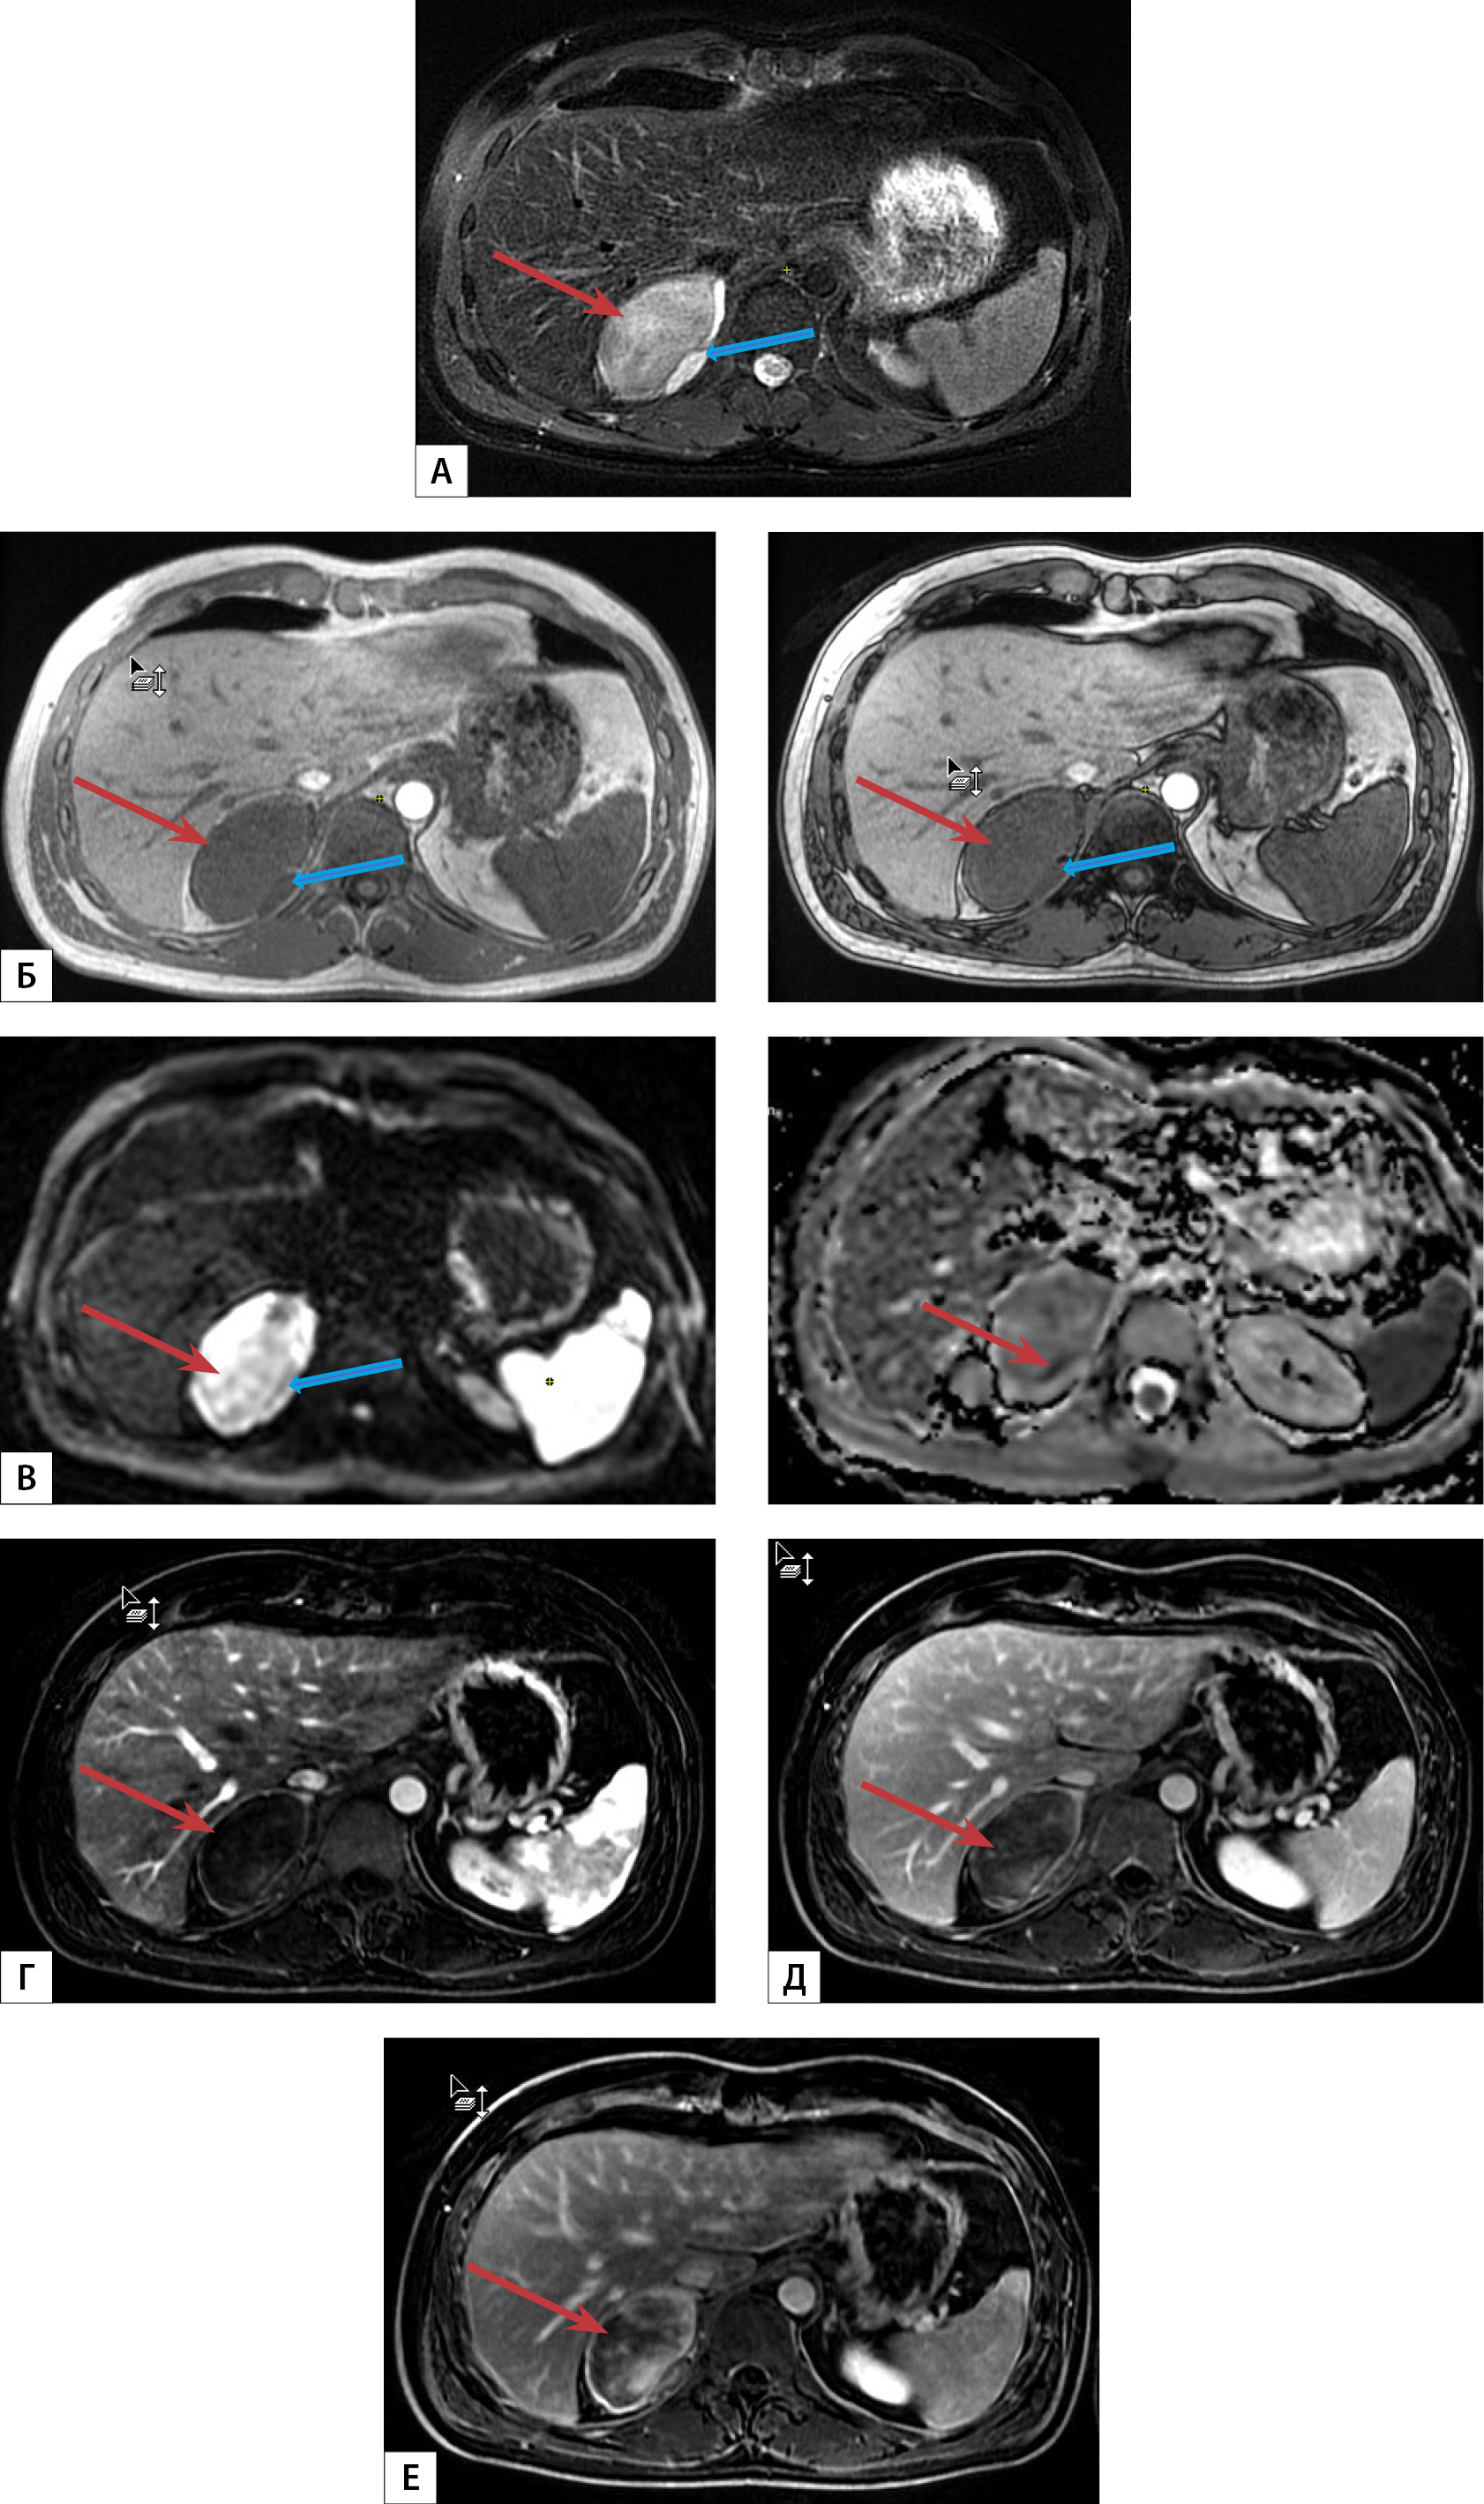

2. Рисунок 2. МРТ надпочечников с внутривенным болюсным контрастированием: А — режим T2-FS, Б — in/out fase, В — DWI/ADC, Г — артериальная фаза, Д — венозная фаза, Е — отсроченная фаза. Образование правого надпочечника (красная стрелка) овальной формы с неровными и четкими контурами, неоднородной структуры, гиперинтенсивного сигнала на DWI, по периферии с участками истинного ограничения диффузии, гиперинтенсивного сигнала на T2-FS, без изменения сигнала на in/out fase, накопление контрастного вещества по периферии образования максимально к отсроченной фазе. По медиальному контуру образования — дополнительная структура вытянутой формы. | |